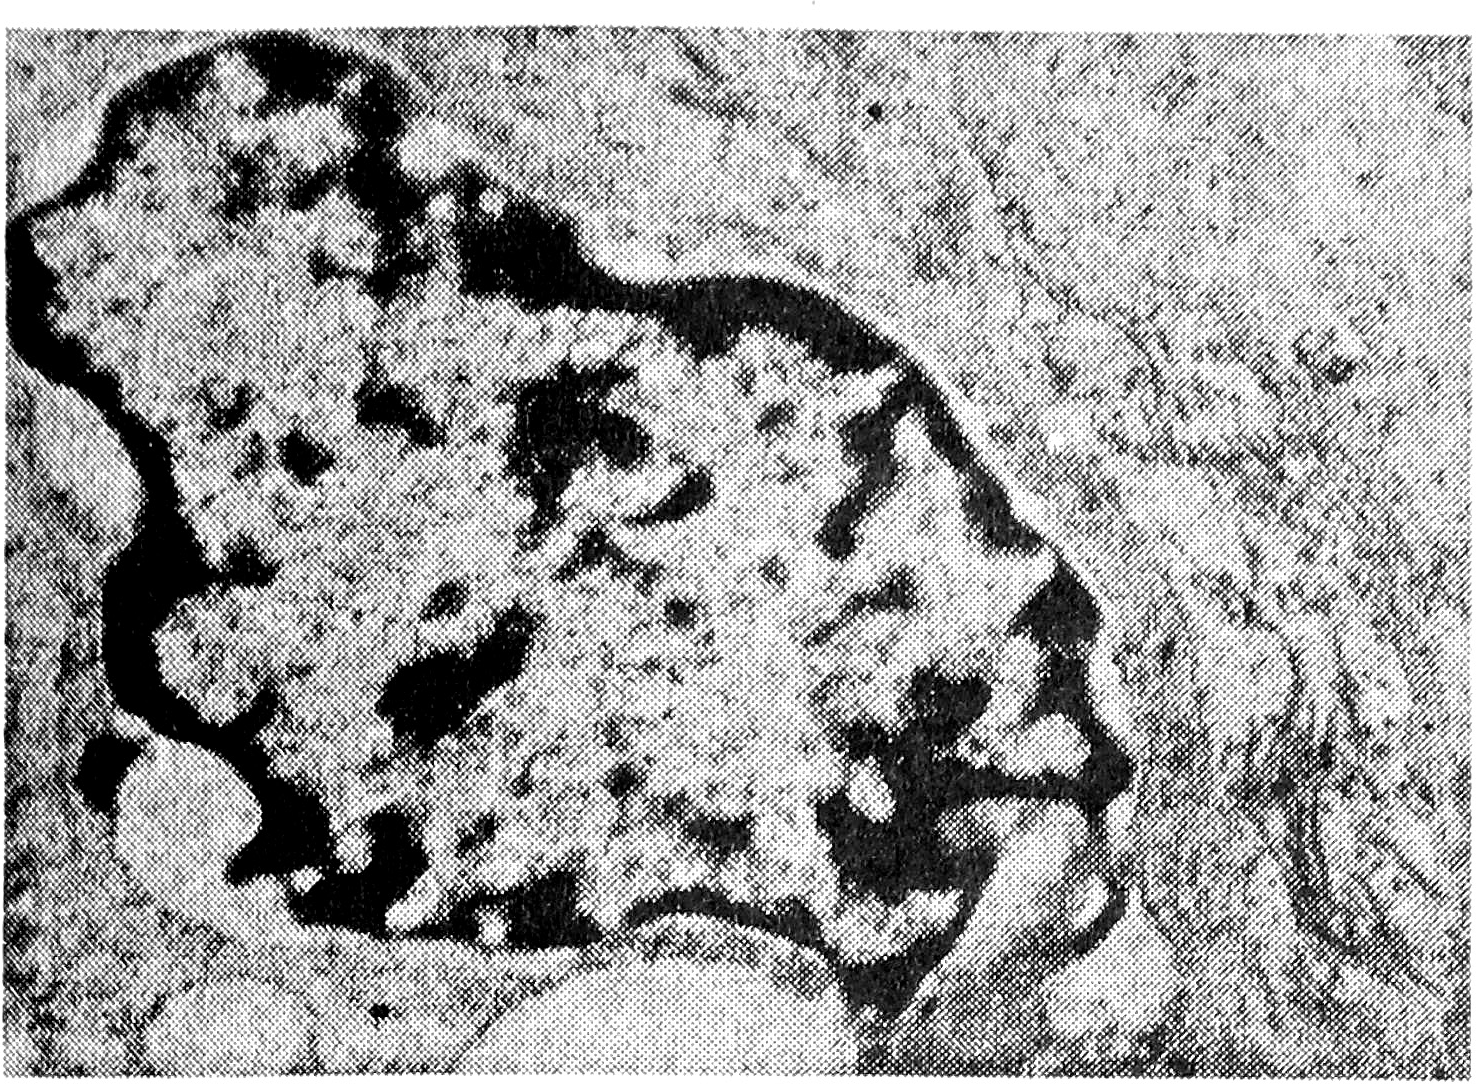

При развивающемся раке обращает на себя внимание прежде всего резкое расширение синусов — их площадь увеличивается до 22,00±0,98% (Р<0,001). Содержание ретикулярных клеток несколько возрастает — 45,25±1,03% (Р<0,001). Под электронным микроскопом данные клеточные элементы выглядят более активными в функциональном отношении. Превалируют фагоцитирующие ретикулярные клетки. Ядро их образует инвагинации; наблюдается краевое расположение ядрышка; в цитоплазме увеличивается содержание свободных рибосом, крупных митохондрий, лизосом и фагоцитированных включений (рис. 3). Параллельно возрастает и количество свободных макрофагов моноцитарного происхождения с ультраструктурными признаками активации и фагоцитоза.

Рис. 3. Фагоцитирующая ретикулярная клетка. X 10000.